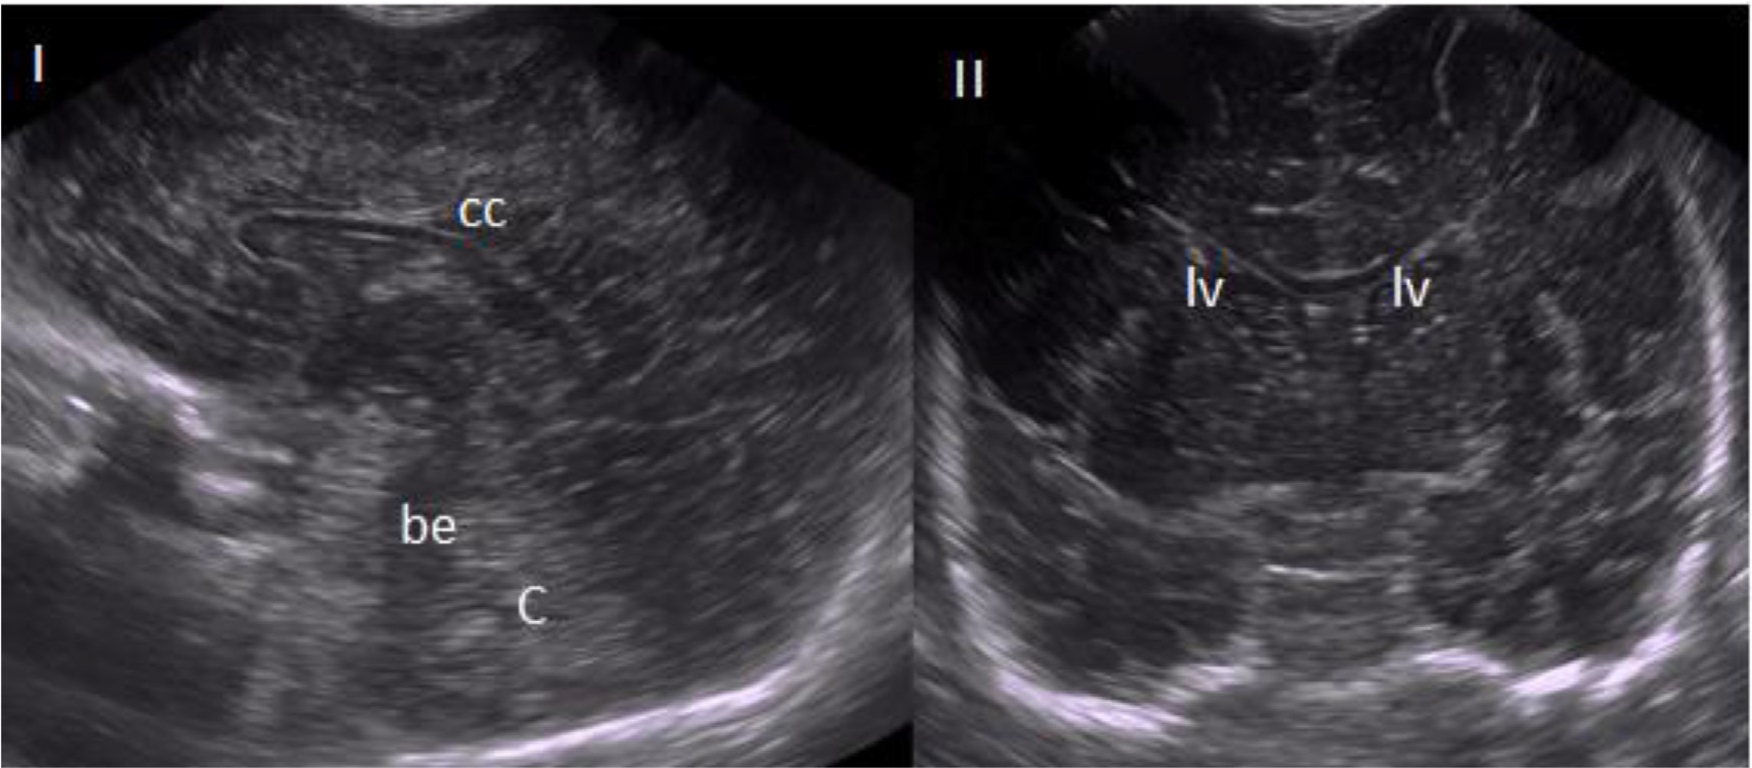

In addition, newborns from the hospital intensive care unit were only enrolled after legal guardians or parents provided written consent. Eight (8) healthy low-risk newborns were included in the study. The procedure was performed in the anterior fontanelle, with the patient in the supine position, and all images were taken in the coronal and sagittal planes. Students were expected to recognize the differences by the sagittal and coronal planes and to determine the corpus callosum, cerebellum, brain stem, and lateral ventricles (Fig. 2).

The main study findings were as follows: according to cognitive evaluation before and after classes, there was learning evolution, with knowledge retention for 6 months; practical training results in a higher number of correct answers and can influence knowledge retention; the capacity to dismiss a normal TU (Fig. 2) was the most difficult parameter for the participants; questions related to the technique of using the USG device were easily addressed and quickly learned by the participants; according to the satisfaction questionnaire, theoretical-practical short-courses are well received by the participants, with even higher results when there is a practical component; and the proposed teaching protocol was well received and can be an interesting way to improve hospital compliance.